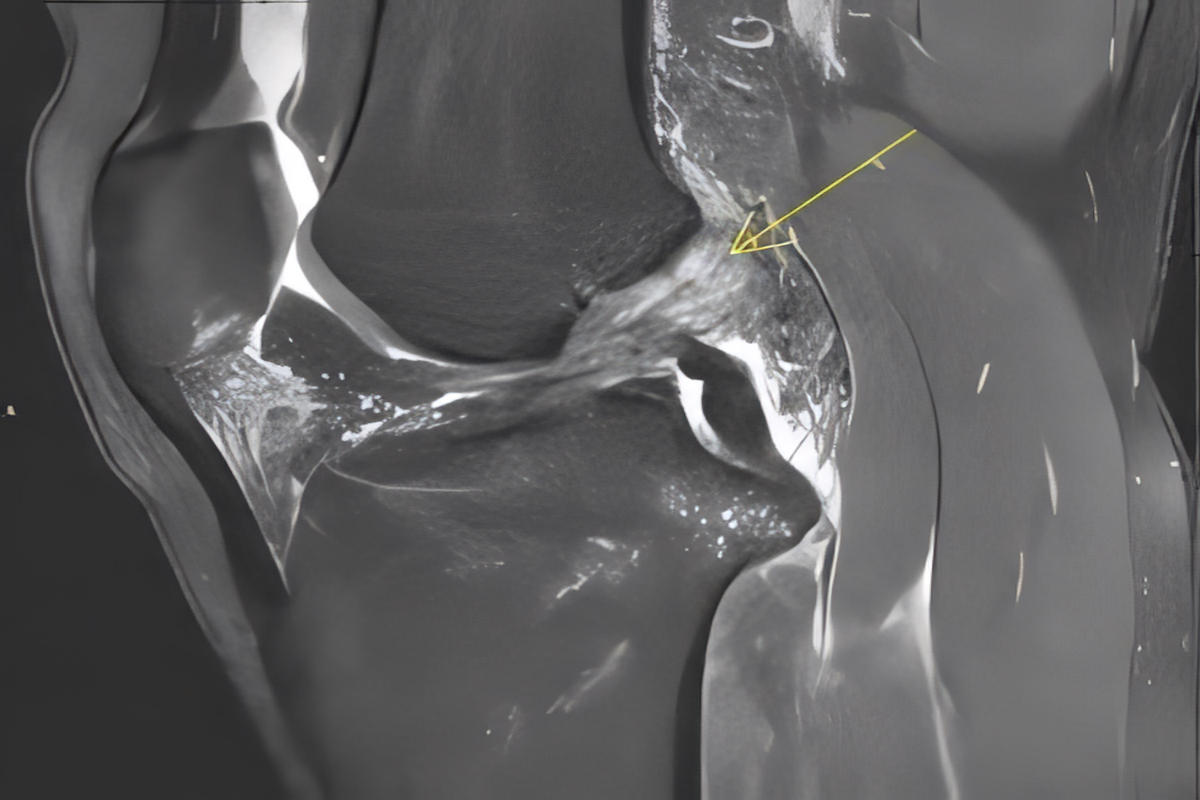

Μαγνητική τομογραφία (MRI), που επιβεβαιώνει τη ρήξη πρόσθιου χιαστού και αναδεικνύει συνοδές βλάβες σε μηνίσκους, χόνδρο ή πλάγιους συνδέσμους

Η MRI αποτελεί την εξέταση εκλογής για την τεκμηρίωση της βλάβης.

Ακτινογραφίες για αποκλεισμό οστικών κακώσεων